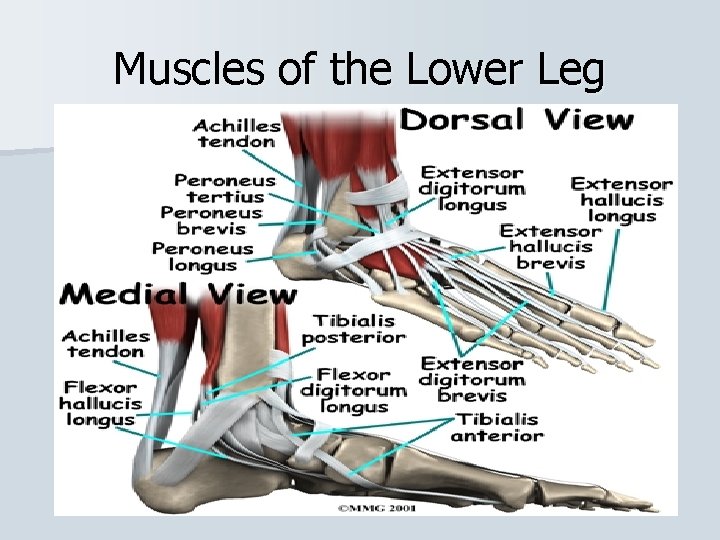

Muscles of the Lower leg

Muscles of the Lower Leg